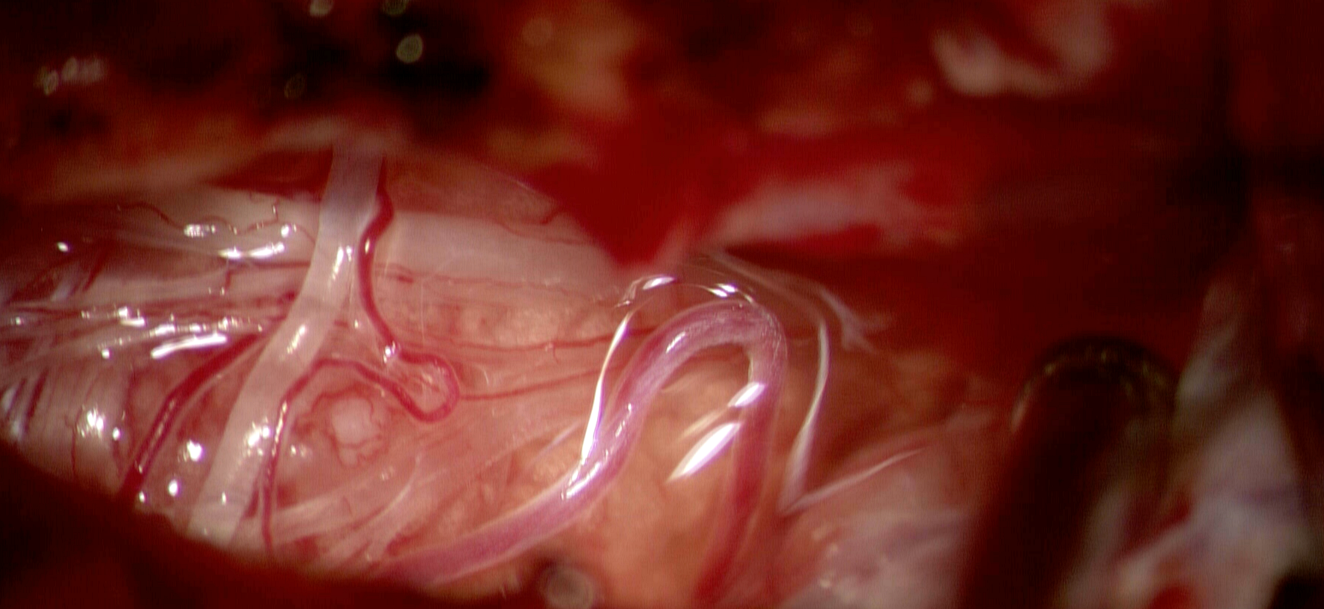

Meduloblastomul este o tumoră neuroectodermală embrionară, clasificată în prezent, conform OMS 2021, ca tumoare malignă de grad IV. Aceasta apare în mod tipic la nivelul cerebelului, mai frecvent în vermis la copii, dar la adult are o predilecție pentru emisferele cerebeloase.

Este caracterizată printr-o creștere rapidă și o tendință de diseminare prin lichidul cefalorahidian (LCR), ceea ce o face o tumoră cu risc de metastazare intracraniană și spinală.

Originea exactă a meduloblastomului este legată de celulele progenitoare neuronale din cerebel. La nivel molecular, sunt implicate mutații genetice care duc la activarea unor căi de semnalizare precum:

- Sonic Hedgehog (SHH)

- WNT/β-catenină

La adult, mutațiile SHH sunt cele mai frecvente și pot fi asociate uneori cu sindroame genetice (ex. sindrom Gorlin), deși majoritatea cazurilor sunt sporadice.